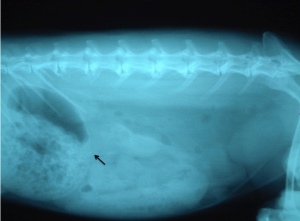

- ウサギの消化管疾患レントゲン像1